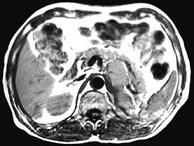

问题 女,34岁,无意中发现血压升高4个月就诊,行CT检查,如图所示,下列说法正确的是 ( )

选项 A、考虑为左肾上腺嗜铬细胞瘤 B、考虑为左肾上腺转移瘤 C、增强扫描,该病灶周边明显强化,中心处强化不明显 D、考虑为左肾上腺腺瘤 E、CT示左侧肾上腺区可见一等密度块影,边界清楚

答案 ACE